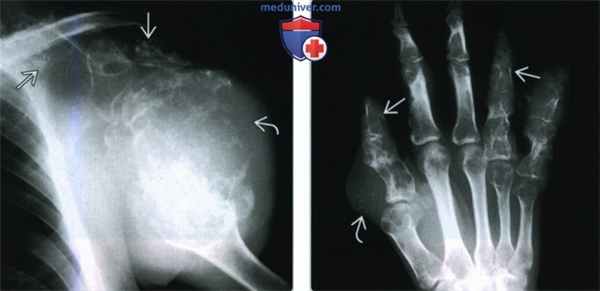

б) Визуализация:

• Асимметричное распределение очагов: до 50% случаев характеризуются односторонней локализацией

• Очаги чаще выявляются в верхней конечности

• Энхондромы:

о Множественные литические очаги вздутия в метафизах, характеризующиеся картообразным склеротическим контуром и хондроидной минерализацией

о Очаги, как правило, располагаются центрально или эксцентрично в полости костного мозга; могут выявляться интракортикально; субпериостальная локализация встречается редко

о Чаще поражаются трубчатые кости, особенно фаланги, пястные и плюсневые кости

о Может выявляться тубулярный очаг, распространяющийся на диафиз от зоны роста; может характеризоваться полосатой структурой

о Хондроидная минерализация в виде точек, дуг, завитков, попкорна и по типу «матового стекла»

• Объемные образования в мягких тканях:

о Гемангиомы при КТ и МРТ: участки жировой ткани; змеевидные тубулярные участки потери сигнала, характеризующиеся контрастным усилением и расположенные в подкожной клетчатке или внутри мышц

о Отличительным признаком очагов является наличие в них флеболитов: кальцинаты при рентгенографии и КТ; гипоинтенсивные участки при МРТ во всех импульсных последовательностях